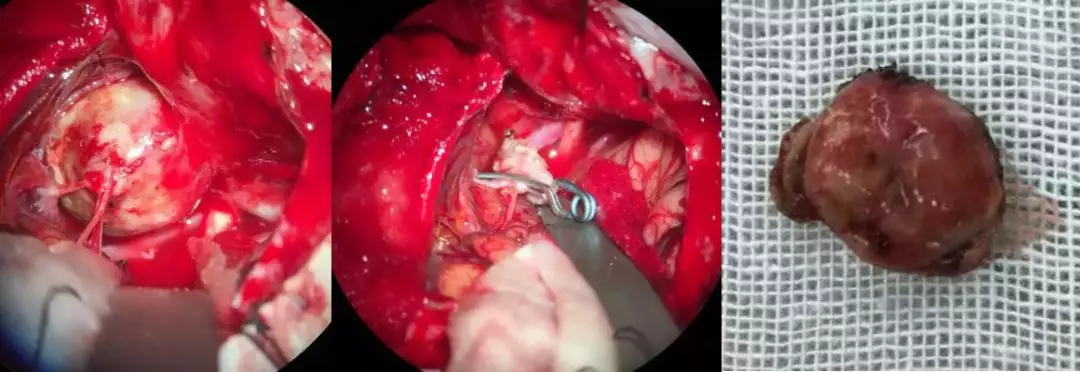

全麻满意后,患者仰卧位,取左侧翼点入路开颅。弧形切开硬膜,显微镜下仔细操作。见脑组织稍膨隆,分离外侧裂,探查见大脑中动脉M2段一巨大球形动脉瘤,直径约2cm,与周围组织粘连紧密,仔细分离粘连,切开瘤体,见瘤腔内形成血栓,清除瘤腔内血栓,切除部分动脉瘤壁,用Mini动脉瘤夹夹闭瘤颈,确认载瘤动脉通畅,用棉纤维包绕残端,手术顺利。